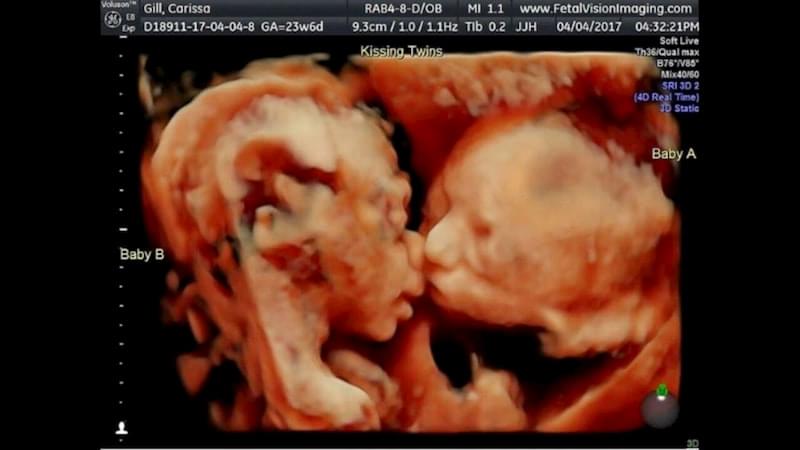

Однояйцевая двойня, или монохориальная двуплодная беременность, зарождается из одной оплодотворенной яйцеклетки, которая в процессе деления образует два эмбриона. Последние развиваются обычно в общей плаценте с двумя отдельными мешками.

У детей одинаковая ДНК, но под воздействием генетики они иногда различаются внешне.

Принято называть близнецами идентичных детей, (хотя это не всегда так). Даже родителям трудно их различить, но это разные личности. Иногда взгляды на жизнь у взрослых однояйцевых близнецов разнятся кардинально.